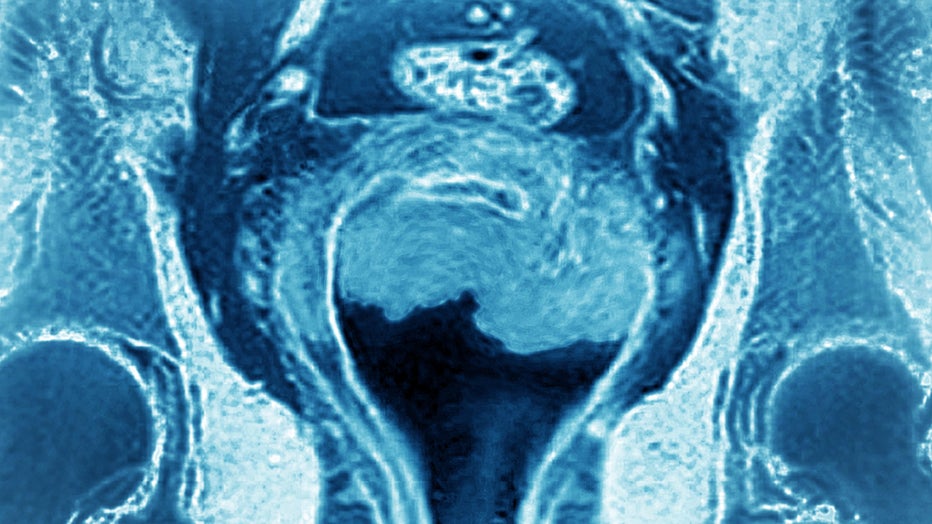

GettyImages-1404559834.jpg

Uterine cancer visualized by frontal MRI. (Photo by: CAVALLINI JAMES/BSIP/Universal Images Group via Getty Images)